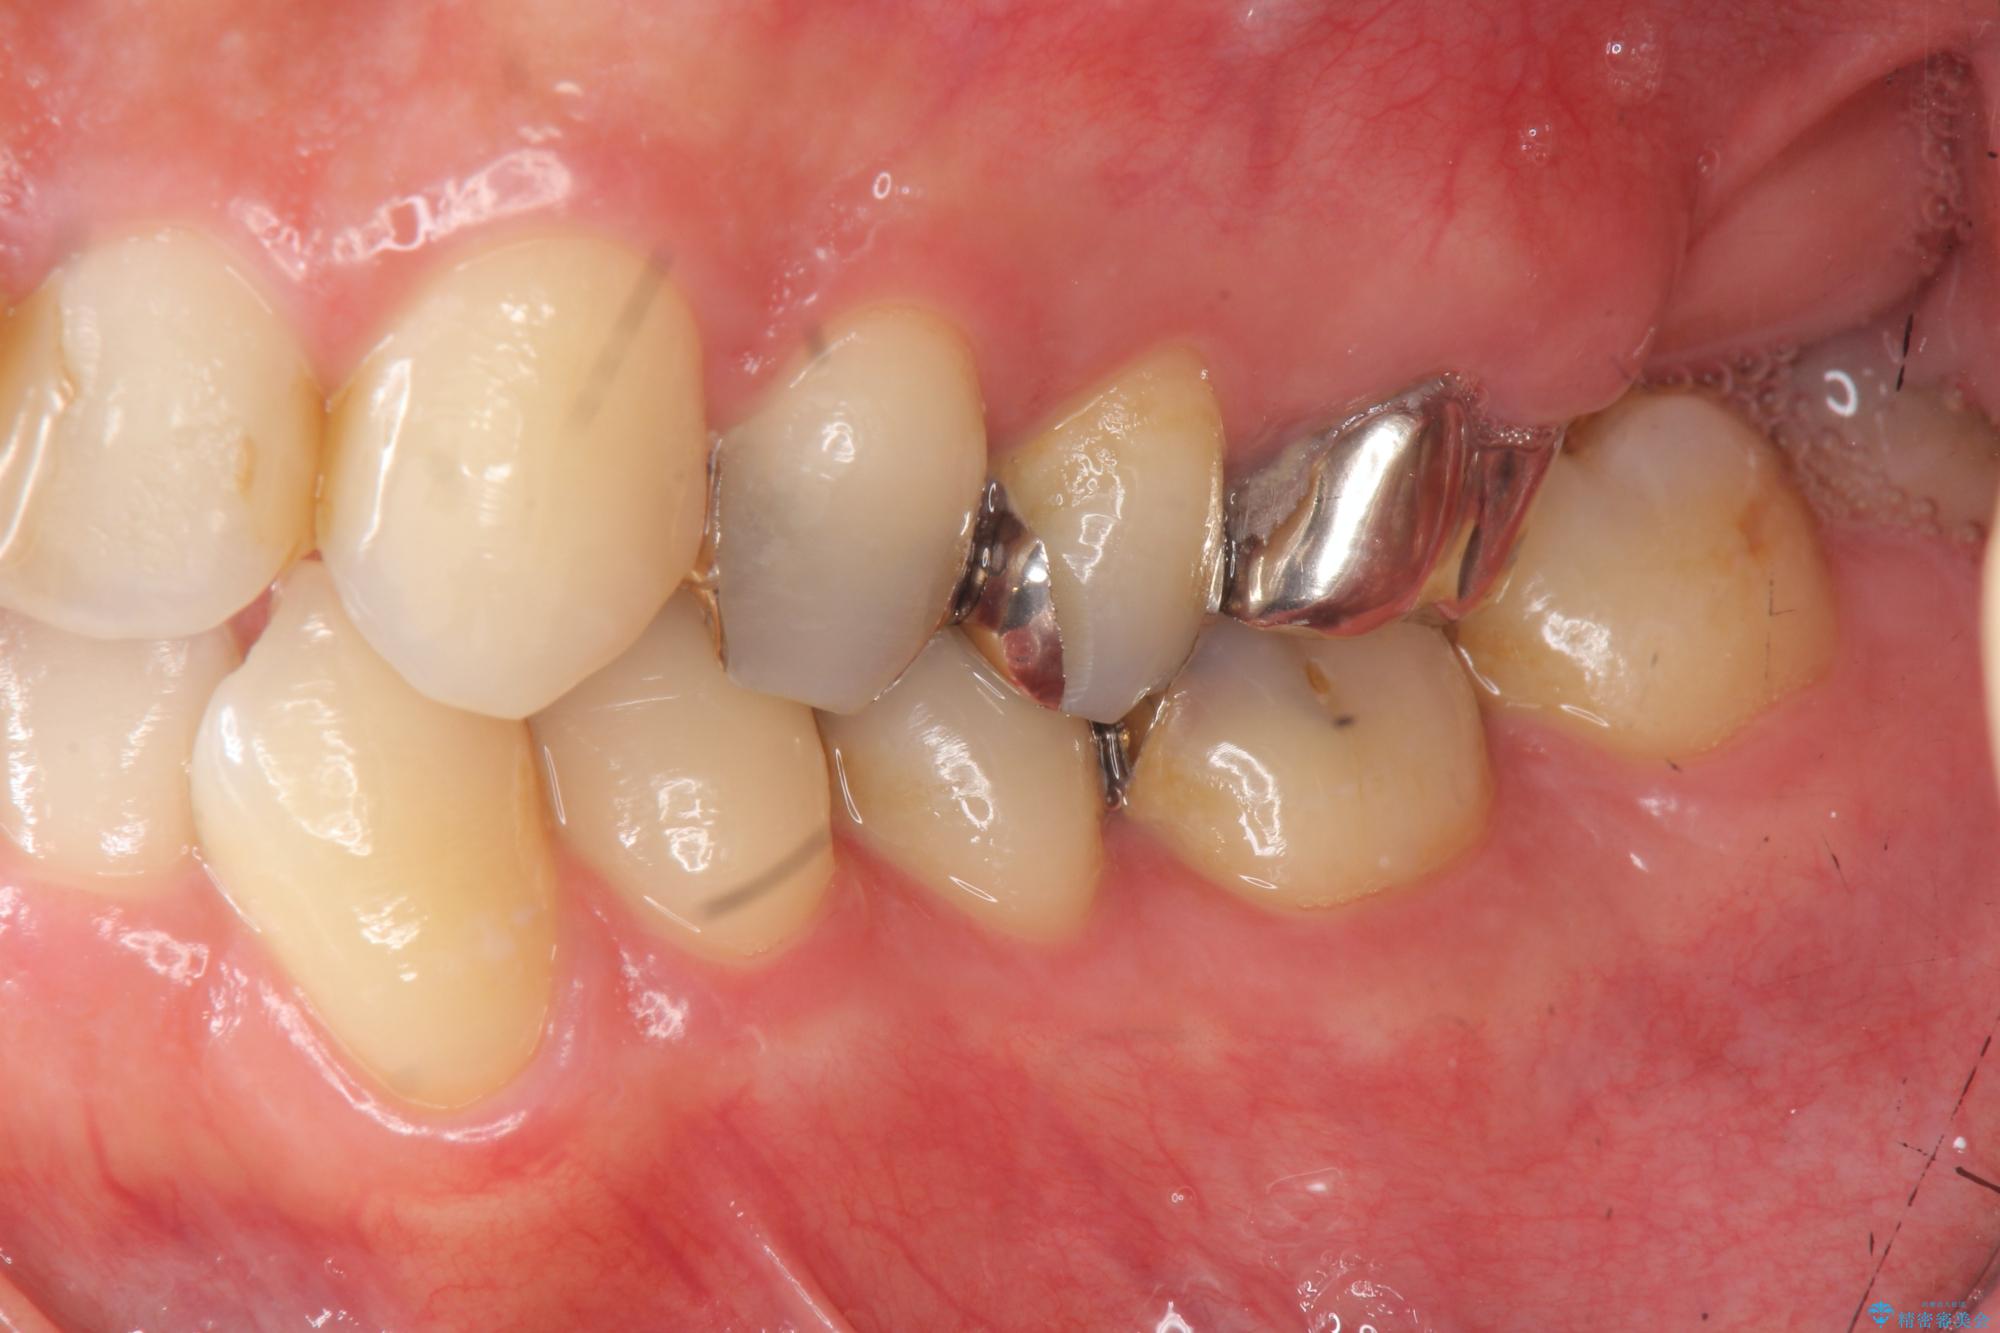

- 突き出た前歯の角度の改善と虫歯治療の改善を求めて来院されました。

虫歯を除去したのち、マウスピース矯正治療を行い、歯並びやがたつきを改善したのち、セラミックに置き換えることで審美性の向上を計画します。